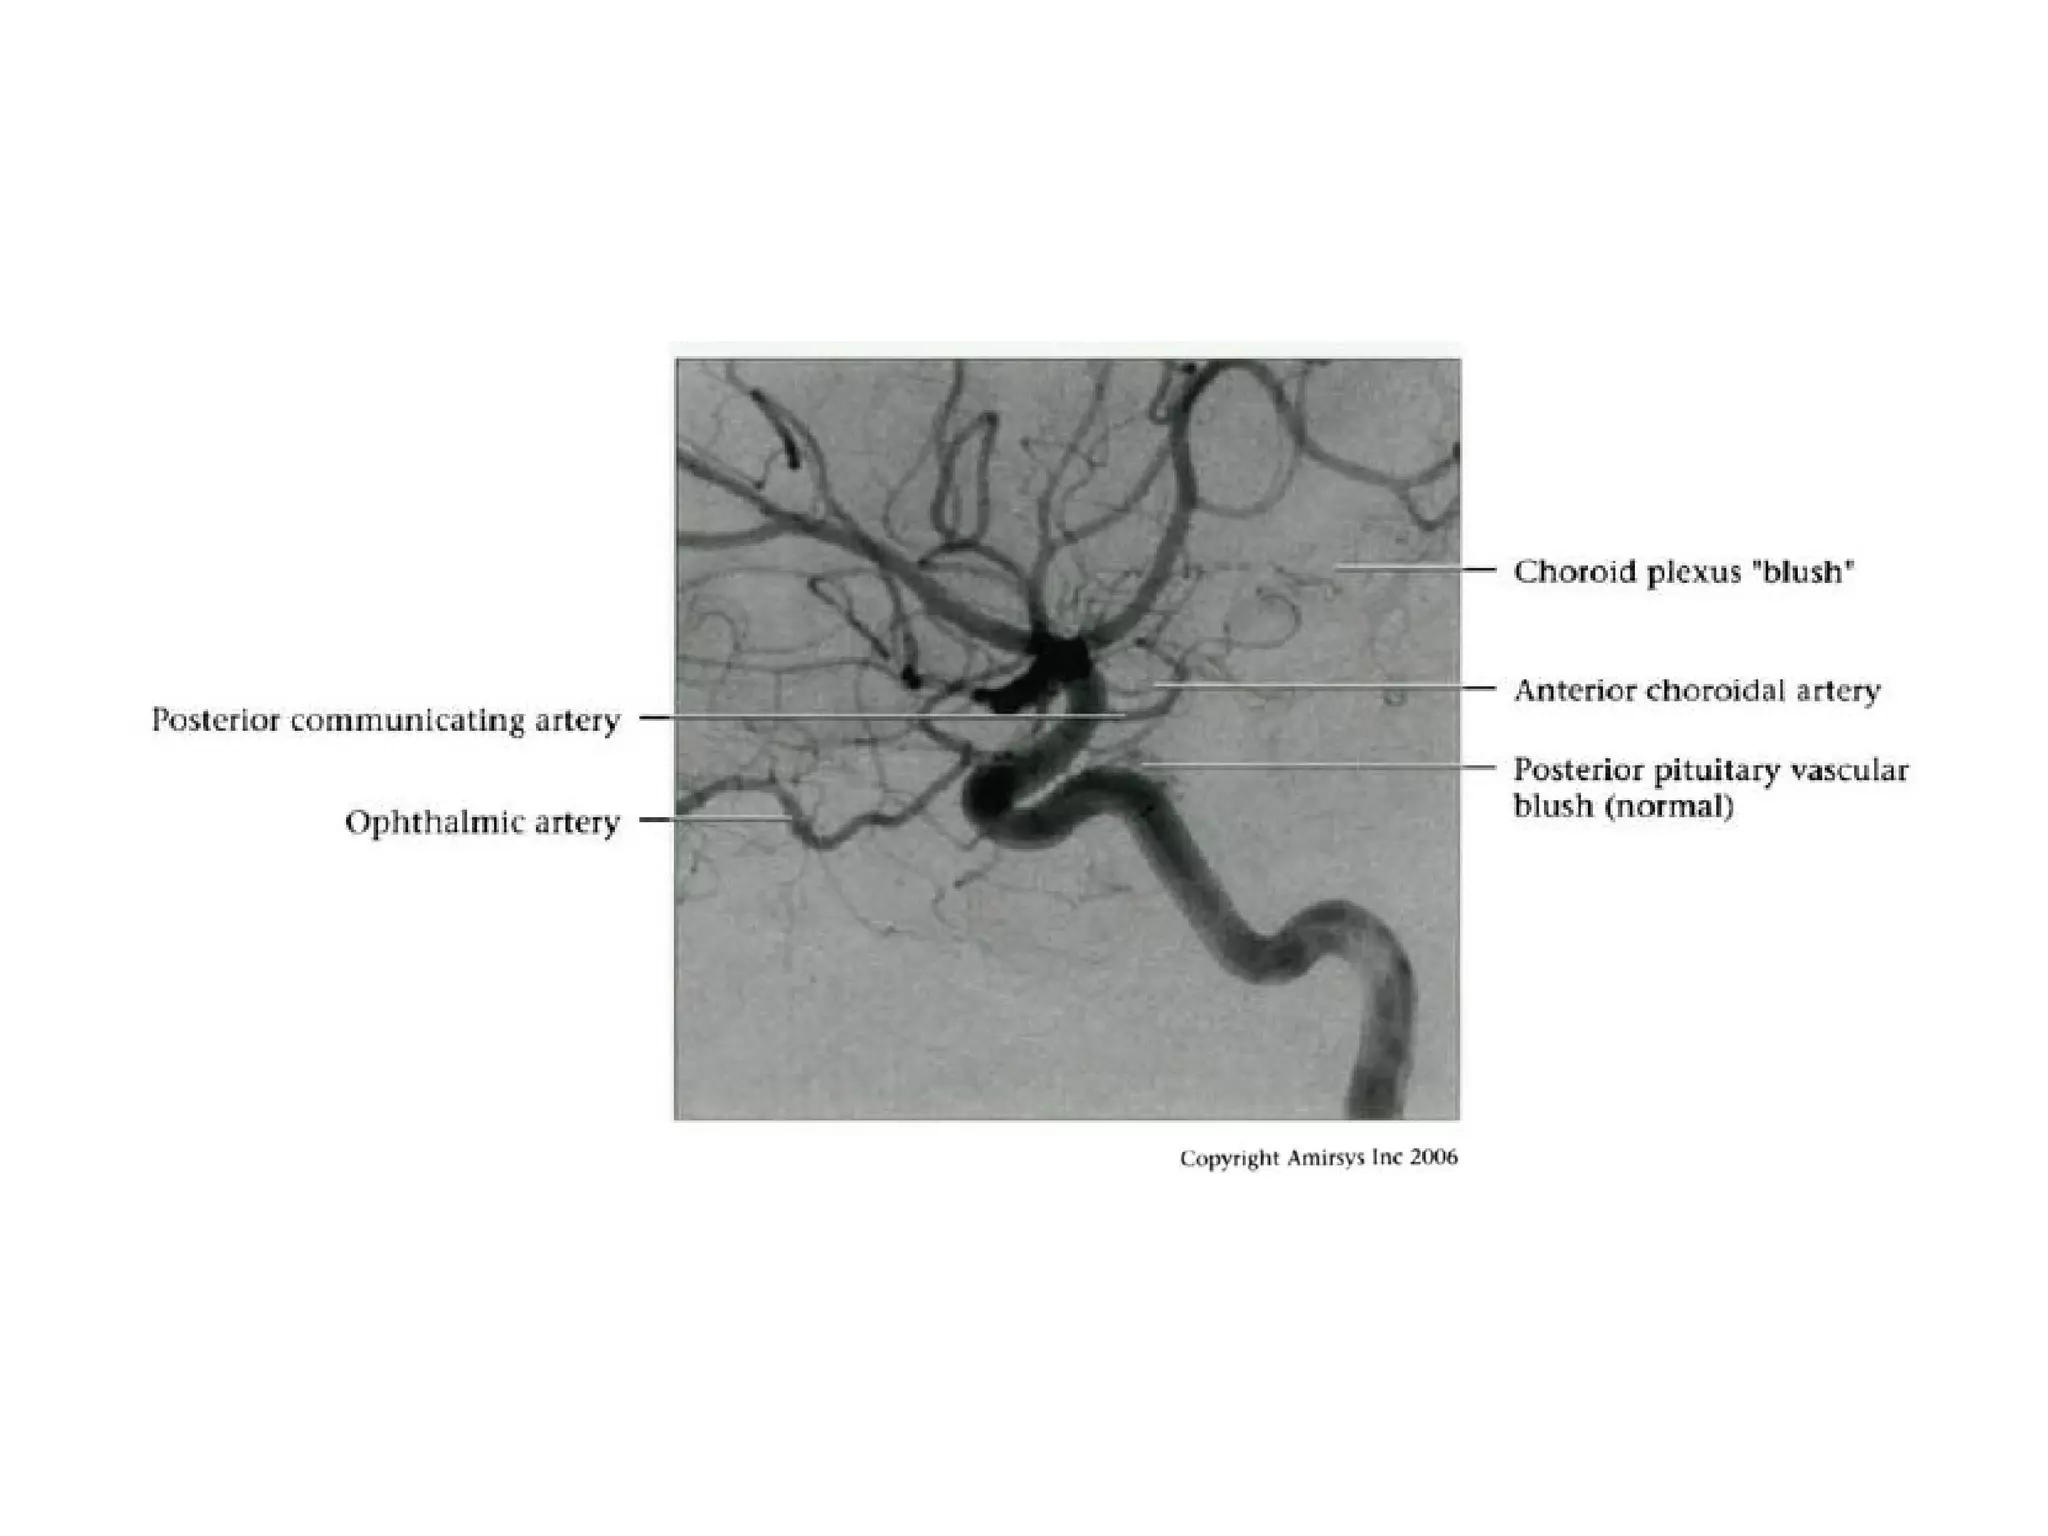

Hyperplastic Anterior

Choroidal Artery

• The anterior choroidal artery, usually a small vessel,

arises from the supraclinoid internal carotid artery just

distal to the posterior communicating artery.

• From there it subdivides into important branches that

supply the cerebral peduncle and optic tract.

• The temporo-occipital branches of the posterior cerebral

artery may arise from the anterior choroidal artery.

• In people with this cerebrovascular variant, the anterior

choroidal artery is described as hyperplastic.

• The prevalence of hyperplastic anterior choroidal arteries

is reported to be 1.1%–2.3%.

RadioGraphics 2009; 29:1027–1043